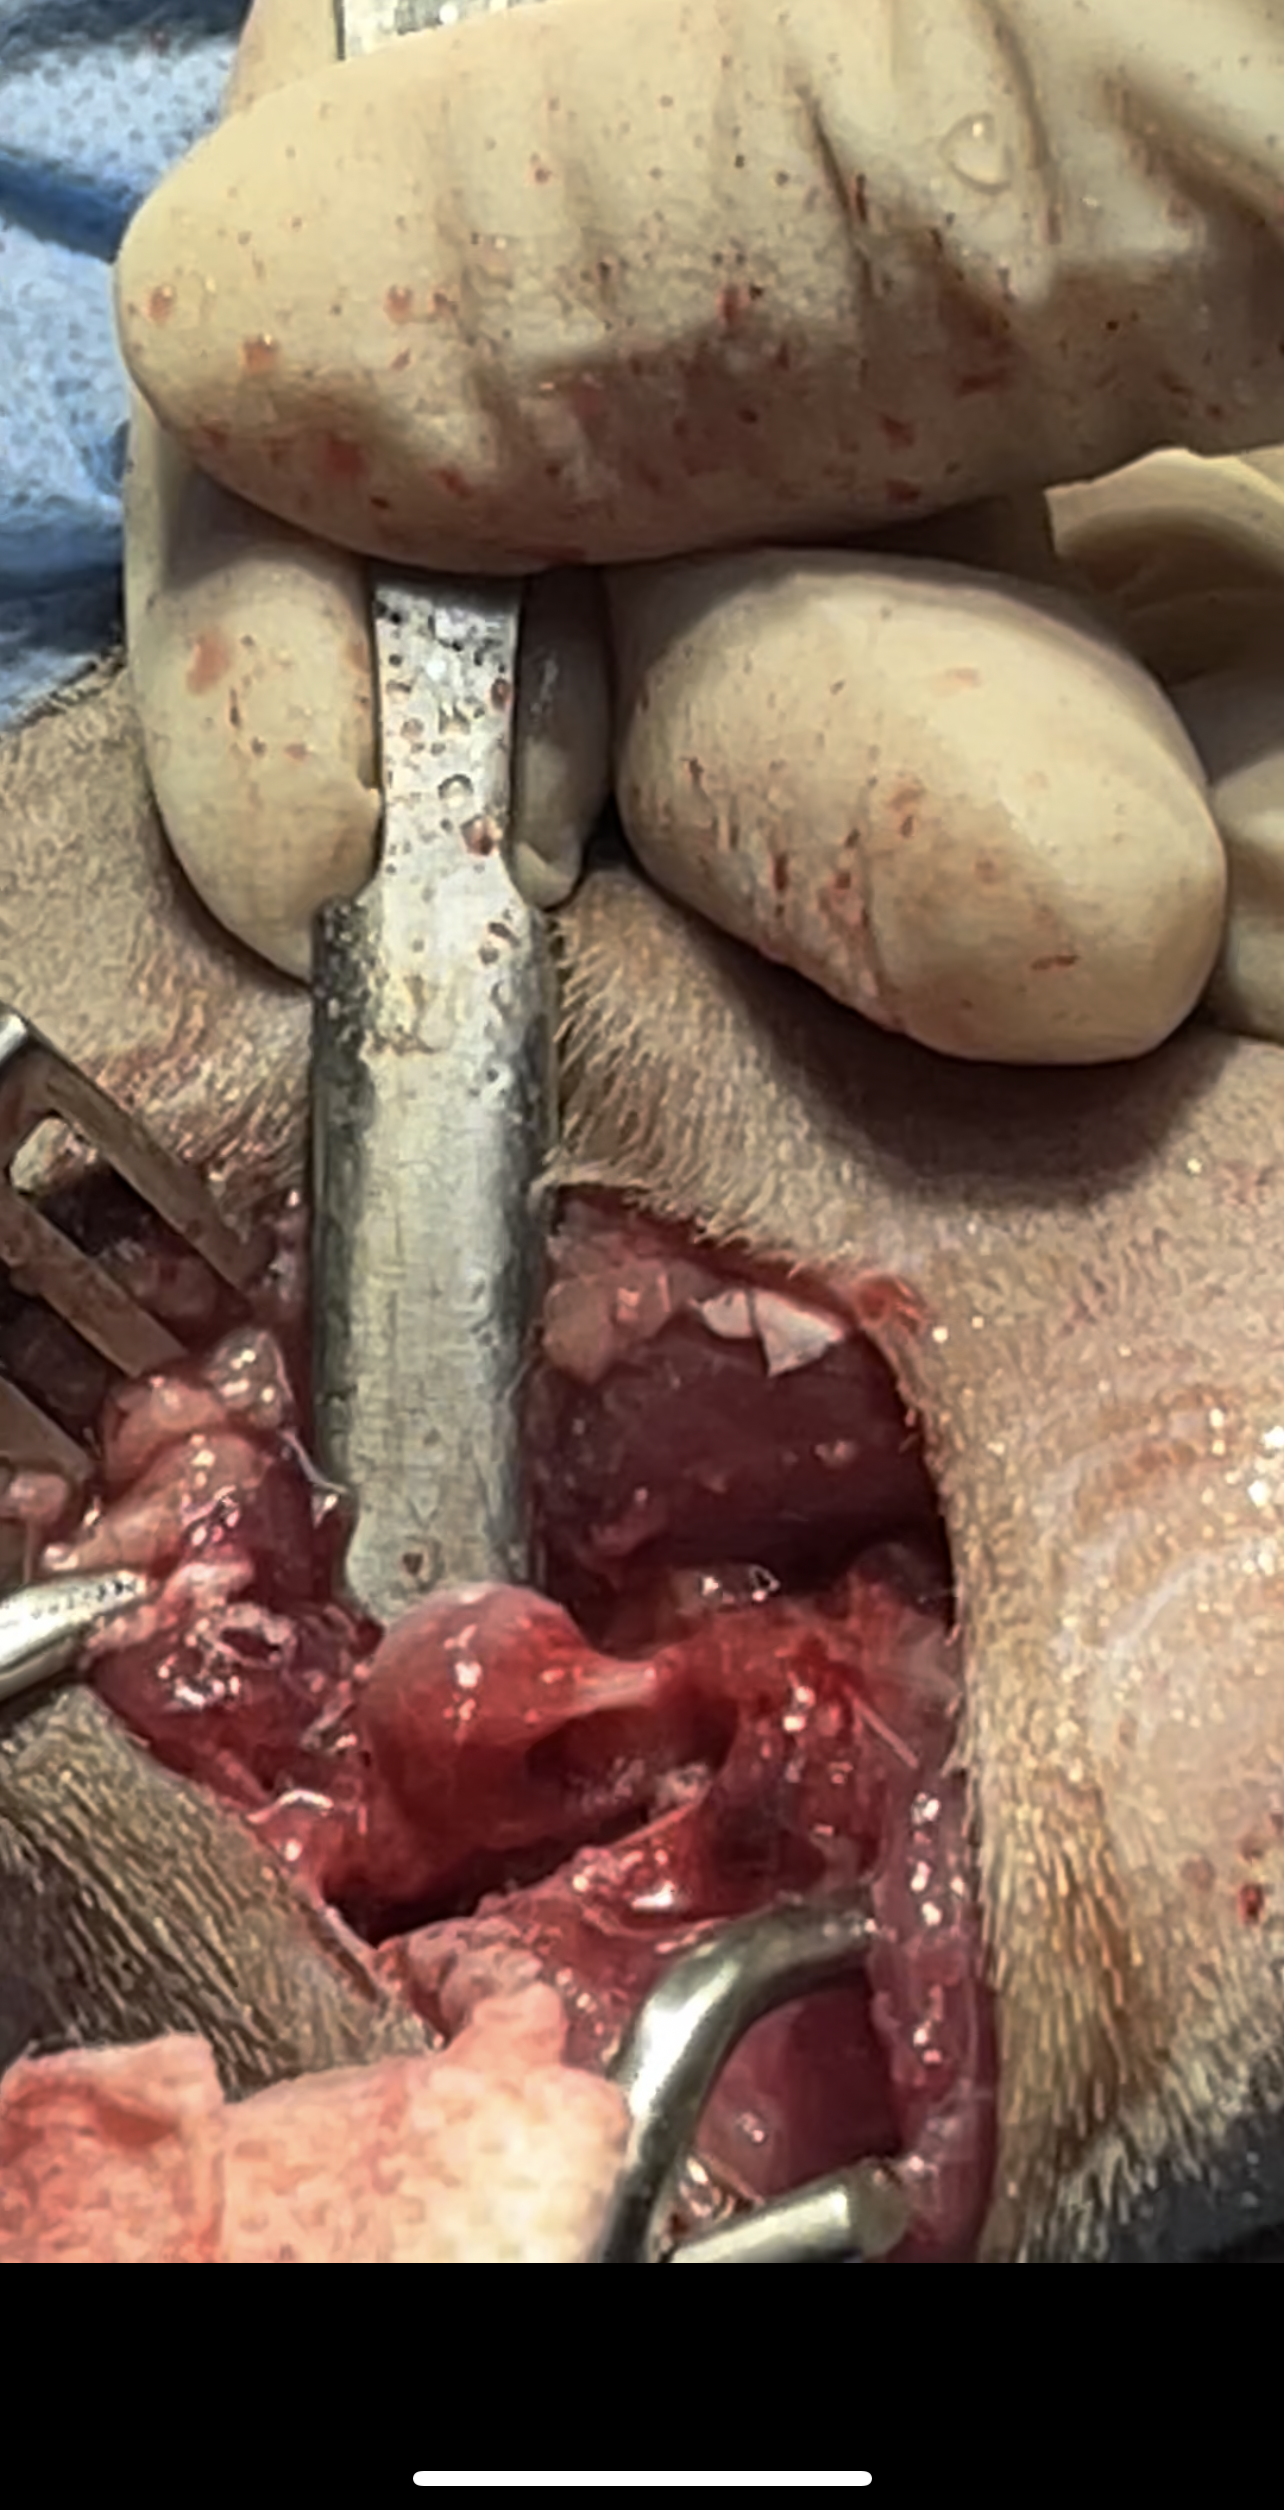

The surgery involves removing the femoral head and neck, thereby eliminating bone-to-bone contact and allowing a fibrous pseudoarthrosis (“false joint”) to form

In cats, particularly lightweight breeds such as the Scottish Shorthair, FHO yields excellent outcomes, even in bilateral cases of hip dysplasia

Bilateral FHO was recommended starting with the right most affected limb and the other to be scheduled after 2 months